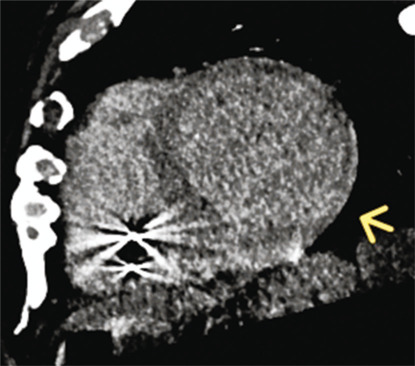

Sarcoidosis is a chronic inflammatory condition of uncertain origins, affecting multiple organs and characterized by the formation of granulomas. Cardiac involvement, known as cardiac sarcoidosis (CS), occurs in 5%-10% of cases and can lead to heart failure, arrhythmias, and sudden death. Distinguishing CS from other heart conditions poses a significant challenge. However, improved diagnostic techniques such as cardiac magnetic resonance (CMR) and positron emission tomography combined with computed tomography (CT) have enhanced recognition rates, replacing invasive procedures like endomyocardial biopsy. Clinical guidelines have further facilitated diagnosis. This case report underscores the diagnostic complexity of CS and highlights the emerging role of contrast-enhanced cardiac CT as a viable alternative to CMR, particularly in patients with contraindications to CMR.